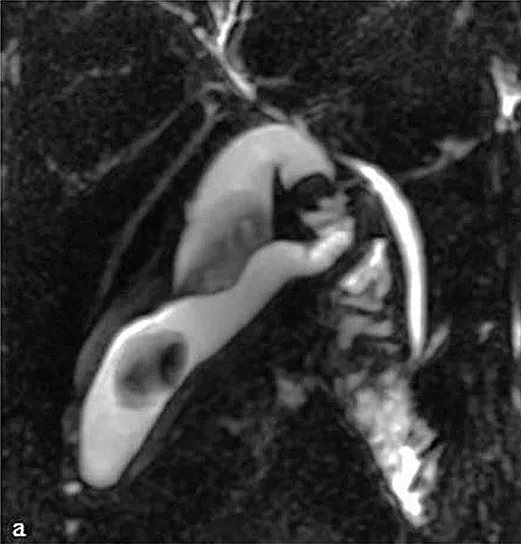

Figure 4 : Aspect en cholangio-IRM des principales variations anatomiques des voies biliaires : trifurcation biliaire (A) ; convergence biliaire étagée avec abouchement direct du canal hépatique antérieur droit (flèche) dans le cholédoque (B) ; canal de Luschka (flèche) compliqué de biliome (étoile) (C) ; gros cholédoque (D)

- Une trifurcation biliaire au niveau de la convergence biliaire due à une agénésie du canal hépatique droit, avec présence de 2 canaux biliaires droits (antérieur et postérieur) reliés directement au canal hépatique gauche pour former le canal hépatique commun (figure 4A) ;

- Une convergence biliaire étagée avec abouchement d’un canal hépatique sectoriel (le plus souvent du foie droit) directement dans la voie biliaire principale (figure 4B) ;

- Un canal hépato-cystique (due à un défaut de séparation entre le bourgeon hépatique et le bourgeon cystique) assurant le drainage biliaire d’un secteur hépatique droit vers la vésicule biliaire ou le canal cystique. Leur fréquence est évaluée à 5 % de la population générale ;

- Le canal de « Luschka » ou canal biliaire sous-vésiculaire, est un canal biliaire aberrant naissant en dehors du parenchyme hépatique, le plus souvent dans l’espace périvésiculaire, et se drainant dans un canal biliaire intra-hépatique, majoritairement du foie droit.

Ces variations anatomiques sont généralement asymptomatiques mais exposent au risque, en cas de cholécystectomie ou de chirurgie hépatique, de plaie biliaire ou de fuite biliaire dans le cas du canal de « Luschka » (figure 4C). La cholangio-IRM pré-opératoire permet le plus souvent de repérer ces variations et de prévenir une éventuelle complication chirurgicale. Cependant, il n’existe pas de donnée justifiant la réalisation systématique d’une cholangio-IRM avant chirurgie vésiculaire, et celle-ci n’est donc pas recommandée.